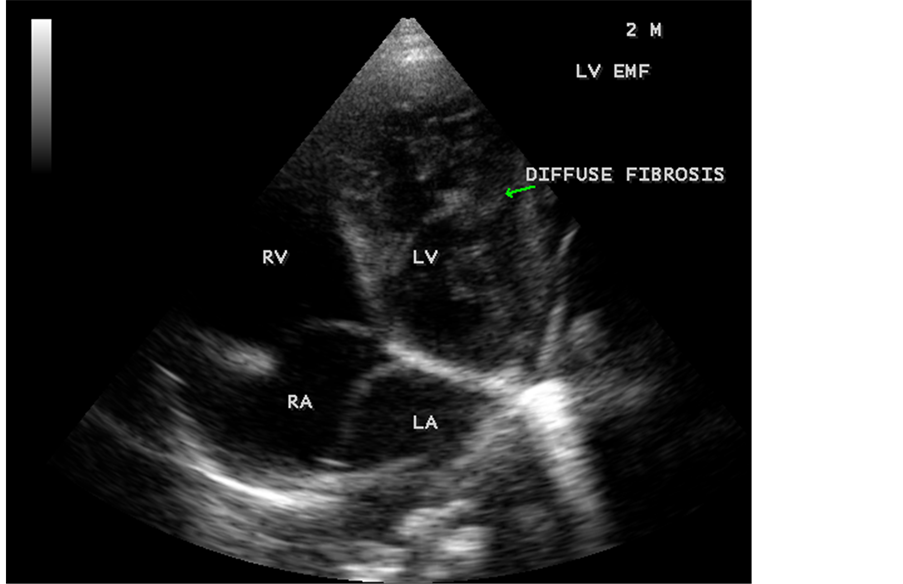

Case 6. Left ventricular endomyocardial fibrosis mimicking as Apical left ventricular hypertrophic cardiomyopathy in a 2-year-old male child as shown in Figure 23, Figure 24 and Figure 25.

Figure 23. Left ventricular endomyocardial fibrosis mimicking as apical left ventricular hypertrophic cardiomyopathy in a 2-year-old male child.

Figure 24. Apical four chamber view showing the endocardial fibrosis of the left ventricle in a 2-year-old male child.

Figure 25. Apical four chamber view showing diffuse endocardial fibrosis of left ventricle in 2-year-old male child.